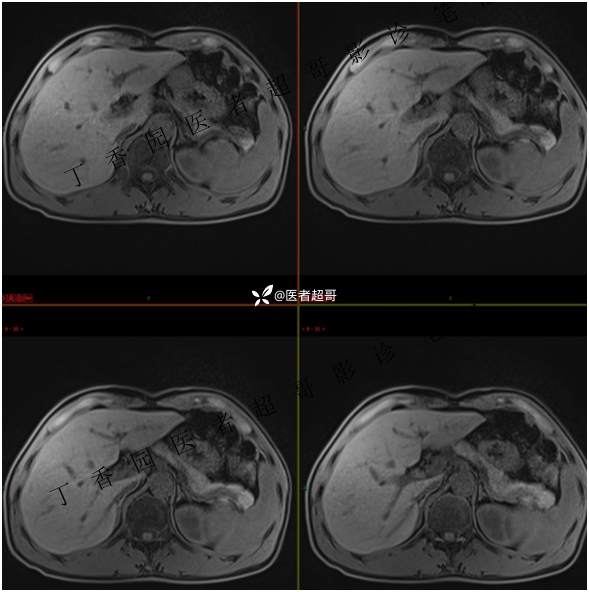

肝胃间隙肿瘤,间质瘤?平滑肌瘤?还是鞘瘤?有结果,请分析!

现病史:患者于3天前查体行肝胆脾胰肾彩超示肝内实性占位,无恶心、呕吐,无发热、寒战,无腹胀、腹泻,进一步于医院行上腹部CT增强示:肝胃交界处肿块。未行特殊治疗。今患者为求进一步治疗,来我院就诊,门诊以“肝占位性病变”收入院。患者自发病以来,神志清,精神可,饮食睡眠可,二便可,体重近期未见明显变化。